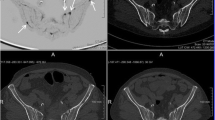

Free-breathing DWI and breath-hold T1-weighted 2-point volume interpolated breath-hold examination (VIBE) Dixon parameters as performed on the institute’s 1.5 T MRI scanner (MAGNETOM Avanto, Siemens Healthineers) are summarised in Table 1. From the VIBE Dixon fat-only (FO) and water-only (WO) images, relative fat fraction (rFF) images were calculated as rFF = \(\frac{FO}{FO+WO}\). Exemplary images as acquired by the described protocol showing acetabular metastases with corresponding CT images are shown in Fig. 2.

CT and multiparametric MRI of a right iliac bone metastasis in a 53-year-old prostate cancer patient. The biopsy tract (upper orange arrow) on the non-contrast (Nc) CT performed after the biopsy was delineated (green) and transferred onto the planning biopsy CT (Bx-CT), relative fat fraction (rFF), diffusion-weighted (DWI) b900 and ADC images. It intersects the delineated metastasis (light red, orange arrow on b50 image)

Right iliac crest metastasis in a 56-year-old prostate cancer patient and multiparametric MRI bone biopsy target selection algorithm, high signal DWI b900 diffusion-weighted images (DWI), low apparent diffusion coefficient (ADC), relative fat fraction (rFF), and consecutive biopsy CT (Bx-CT). Note that despite the sclerotic CT appearance, the biopsy samples were suitable for next-generation genomic sequencing